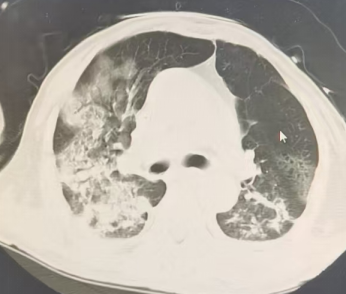

2025-10-22胸部CT:气管插管术后,气管腔内可见高密度影附着。桶状胸廓,双肺可见多发类圆形无壁及薄壁透光区,双肺内可见散在斑片状稍高密度影,边缘模糊不清,部分实变。双侧胸腔内可见弧形液体密度影。主动脉及冠状动脉走行区可见致密影。双侧胸腔内未见积液。